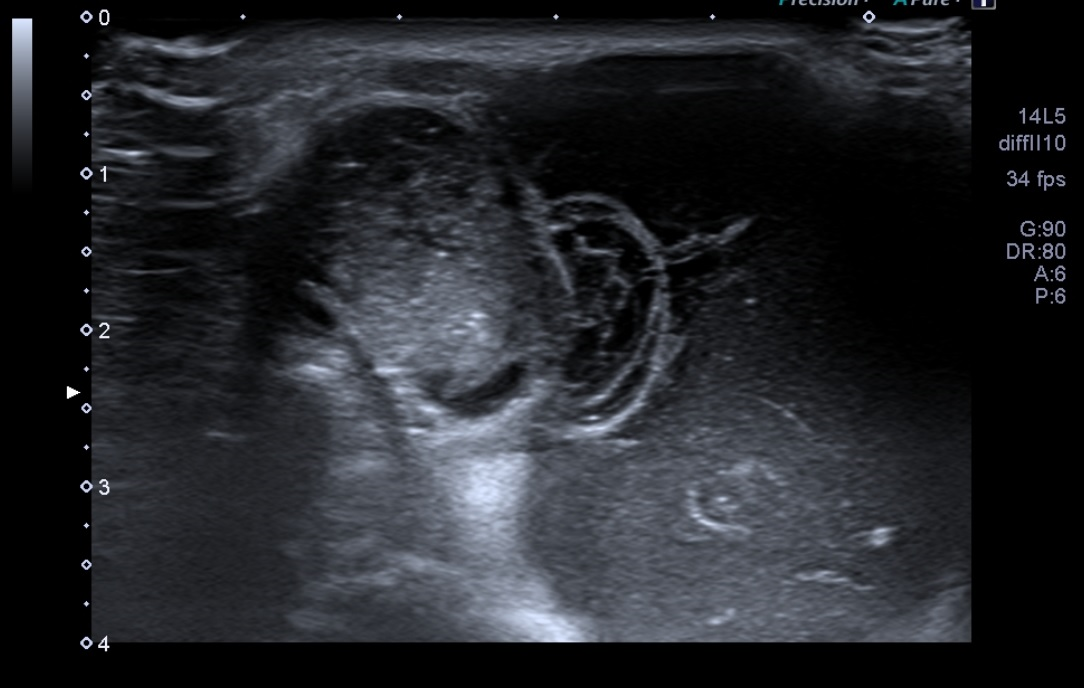

Ante la sospecha de quiste sinovial se realiza Ecografía músculo esquelética en consulta.

Difícil acceso por las forma de la masa. Se observa en plano dérmico lesión sin pared de 1,85 cm en su mayor altura, aneicoica con flóculos en su interior. No parece depender de la articulación del hombro ni la acromionclavicular, no se aportan más medidas por salirse de la ventana del ecógrafo.

Ecografía de Radiología: La masa que se palpa en el hombro izquierdo se corresponde con una masa quística que nace desde la articulación acromionclavicular en relación con rotura del manguito de los rotadores identificándose compromiso del supra e infraespinoso.